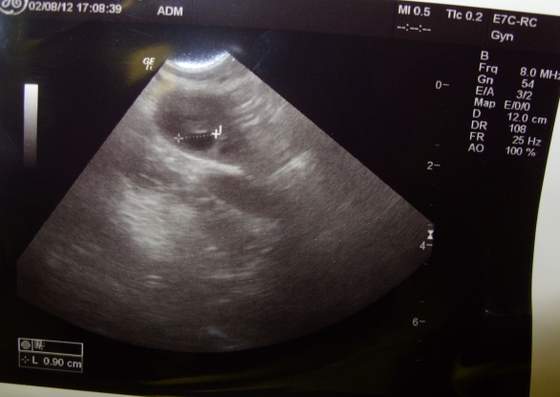

haha jajniczek lewy mam pęcherzyk graafa o proszę bardzo : Zobacz załącznik 487581 jeszcze przez 2-3 dni będzie rósł, ale niestety mam stan zapalny i musze się wyleczyć - potem dopiero przytulanki. Mąż dostał skierowanie na badanie nasienia bo chcieliśmy musimy zadzwonić i sie umówić .. następna wizyta 30.08 i kazała przyjechać z wynikami i będziemy działać jak wszystko będzie dobrze